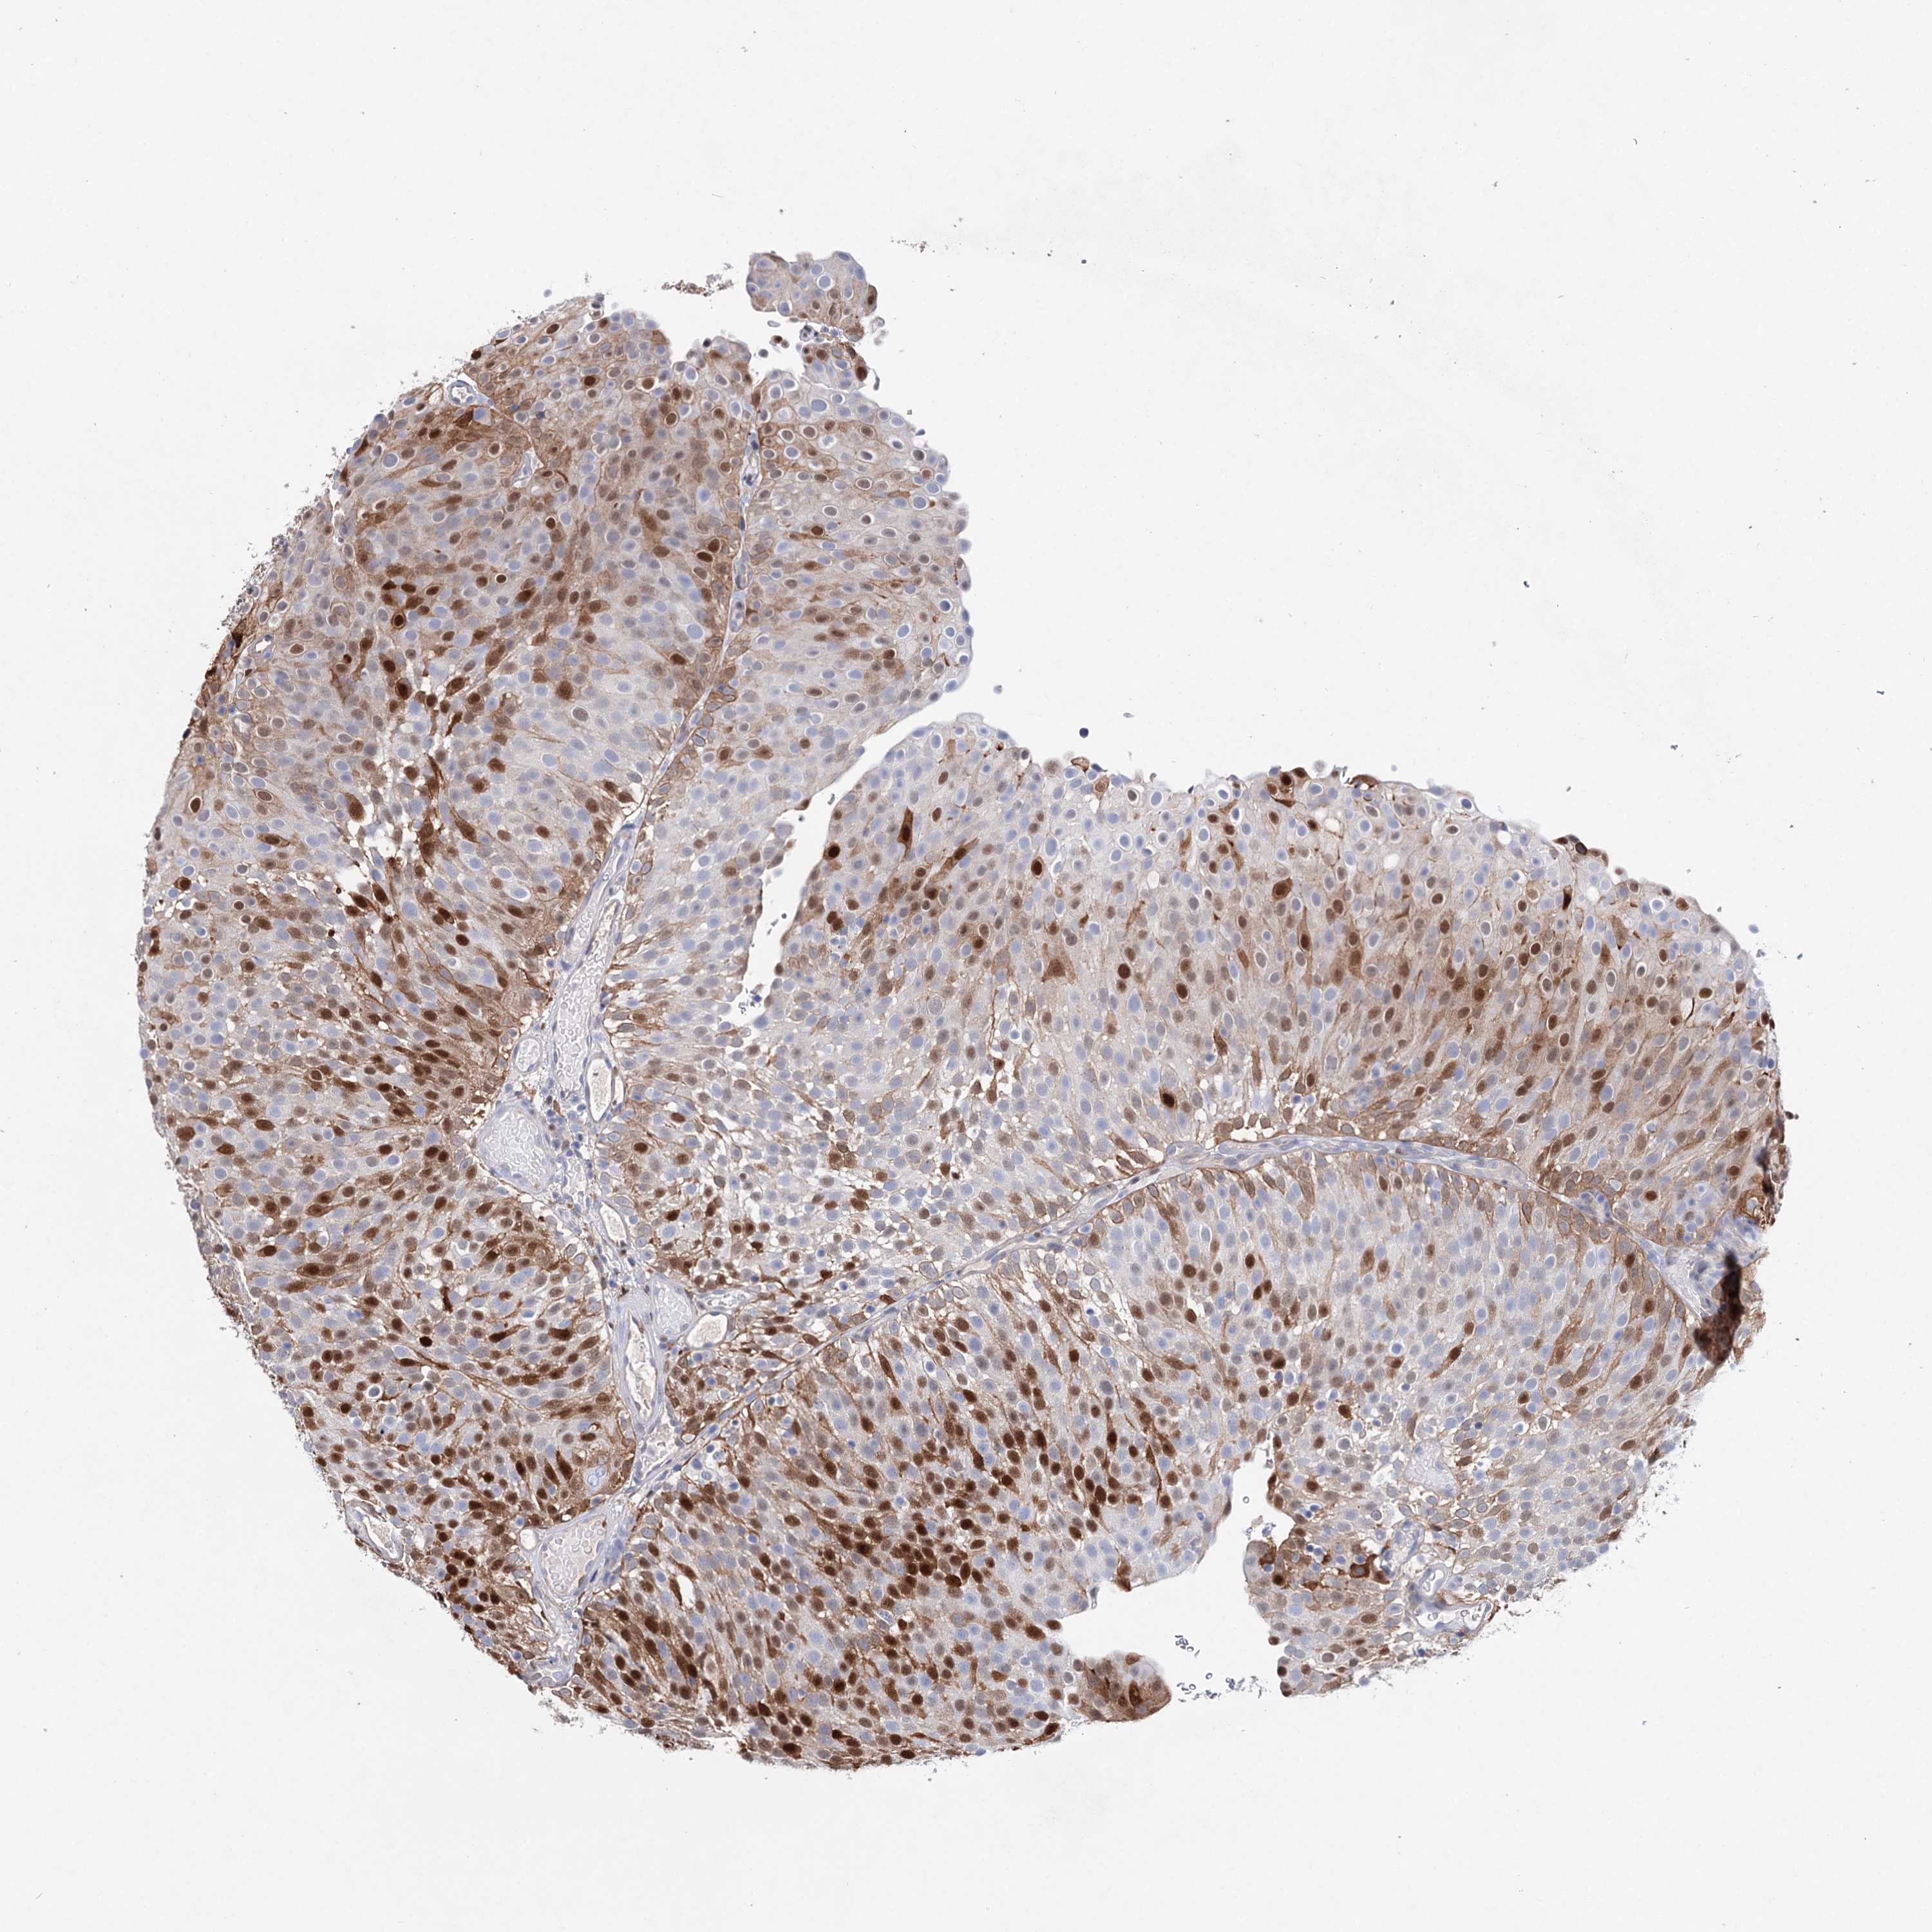

UROTHELIAL CANCER - Protein expressioni

A mouse-over function shows sample information and annotation data. Click on an image to view it in a full screen mode. Samples can be filtered based on level of antibody staining by selecting one or several of the following categories: high, medium, low and not detected. The assay and annotation is described here.

Note that samples used for immunohistochemistry by the Human Protein Atlas do not correspond to samples in the TCGA dataset.

Antibody stainingi

Antibody staining in the annotated cell types in the current human tissue is reported as not detected, low, medium, or high, based on conventional immunohistochemistry profiling in selected tissues. This score is based on the combination of the staining intensity and fraction of stained cells.

Each image is clickable and will lead to virtual microscopy that enables deeper exploration of all samples and also displays staining intensity scores, fraction scores and subcellular localization as well as patient and tissue information for each sample.

Antibody HPA037786

Antibody HPA038034

Antibody HPA038867

Antibody HPA038868

Staining

High

Medium

Low

Not detected

Intensity

Strong

Moderate

Weak

Negative

Quantity

>75%

75%-25%

<25%

None

Location

Nuclear

Cytoplasmic/membranous

Cytoplasmic/membranous,nuclear

Urothelial carcinoma, High grade

Urothelial carcinoma, Low grade

Urothelial carcinoma, NOS